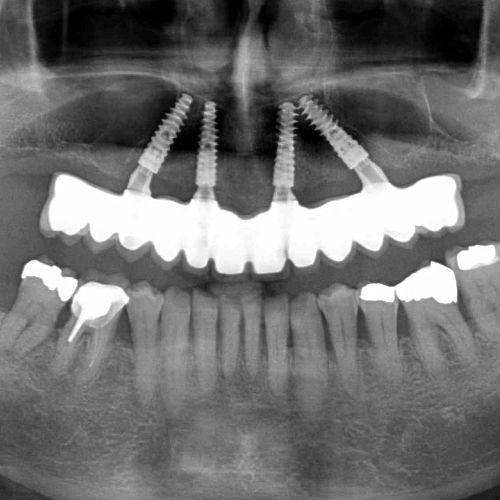

A legjobb megoldás, amikor 6-8 implantátumot az állcsontba ültetve egy fix híd készülhet a fogsor helyére.

Ideális esetben 8 implantátumra készülhet a 12 fogat pótló híd, mely teljesen rögzített a szájban. A páciens ezt nem tudja eltávolítani.

Ha a páciens már régen elvesztette a fogait az az eset állhat elő, hogy a csontfelszívódás miatt már nem lehet fix megoldást készíteni, mert az állkapocs elülső részén is felszívódott a csont. Ebben az esetben 2-3-4 implantátum beültetése után ezekre az implantátumokra egy speciálisan készített fogsort, az úgynevezett overdenture-t lehet rögzíteni.

Ennél a megoldásnál egy fix csavarozott stég kerül az implantátumokra, erre rögzül a fogsor, mely jellegében a hagyományos műfogsorra hasonlít, de az implantátum miatt annál sokkal stabilabb, és egyáltalán nem mozog. Ezenkívül az implantátumok itt is stimulálják a csontot, tehát megáll a csont sorvadása.